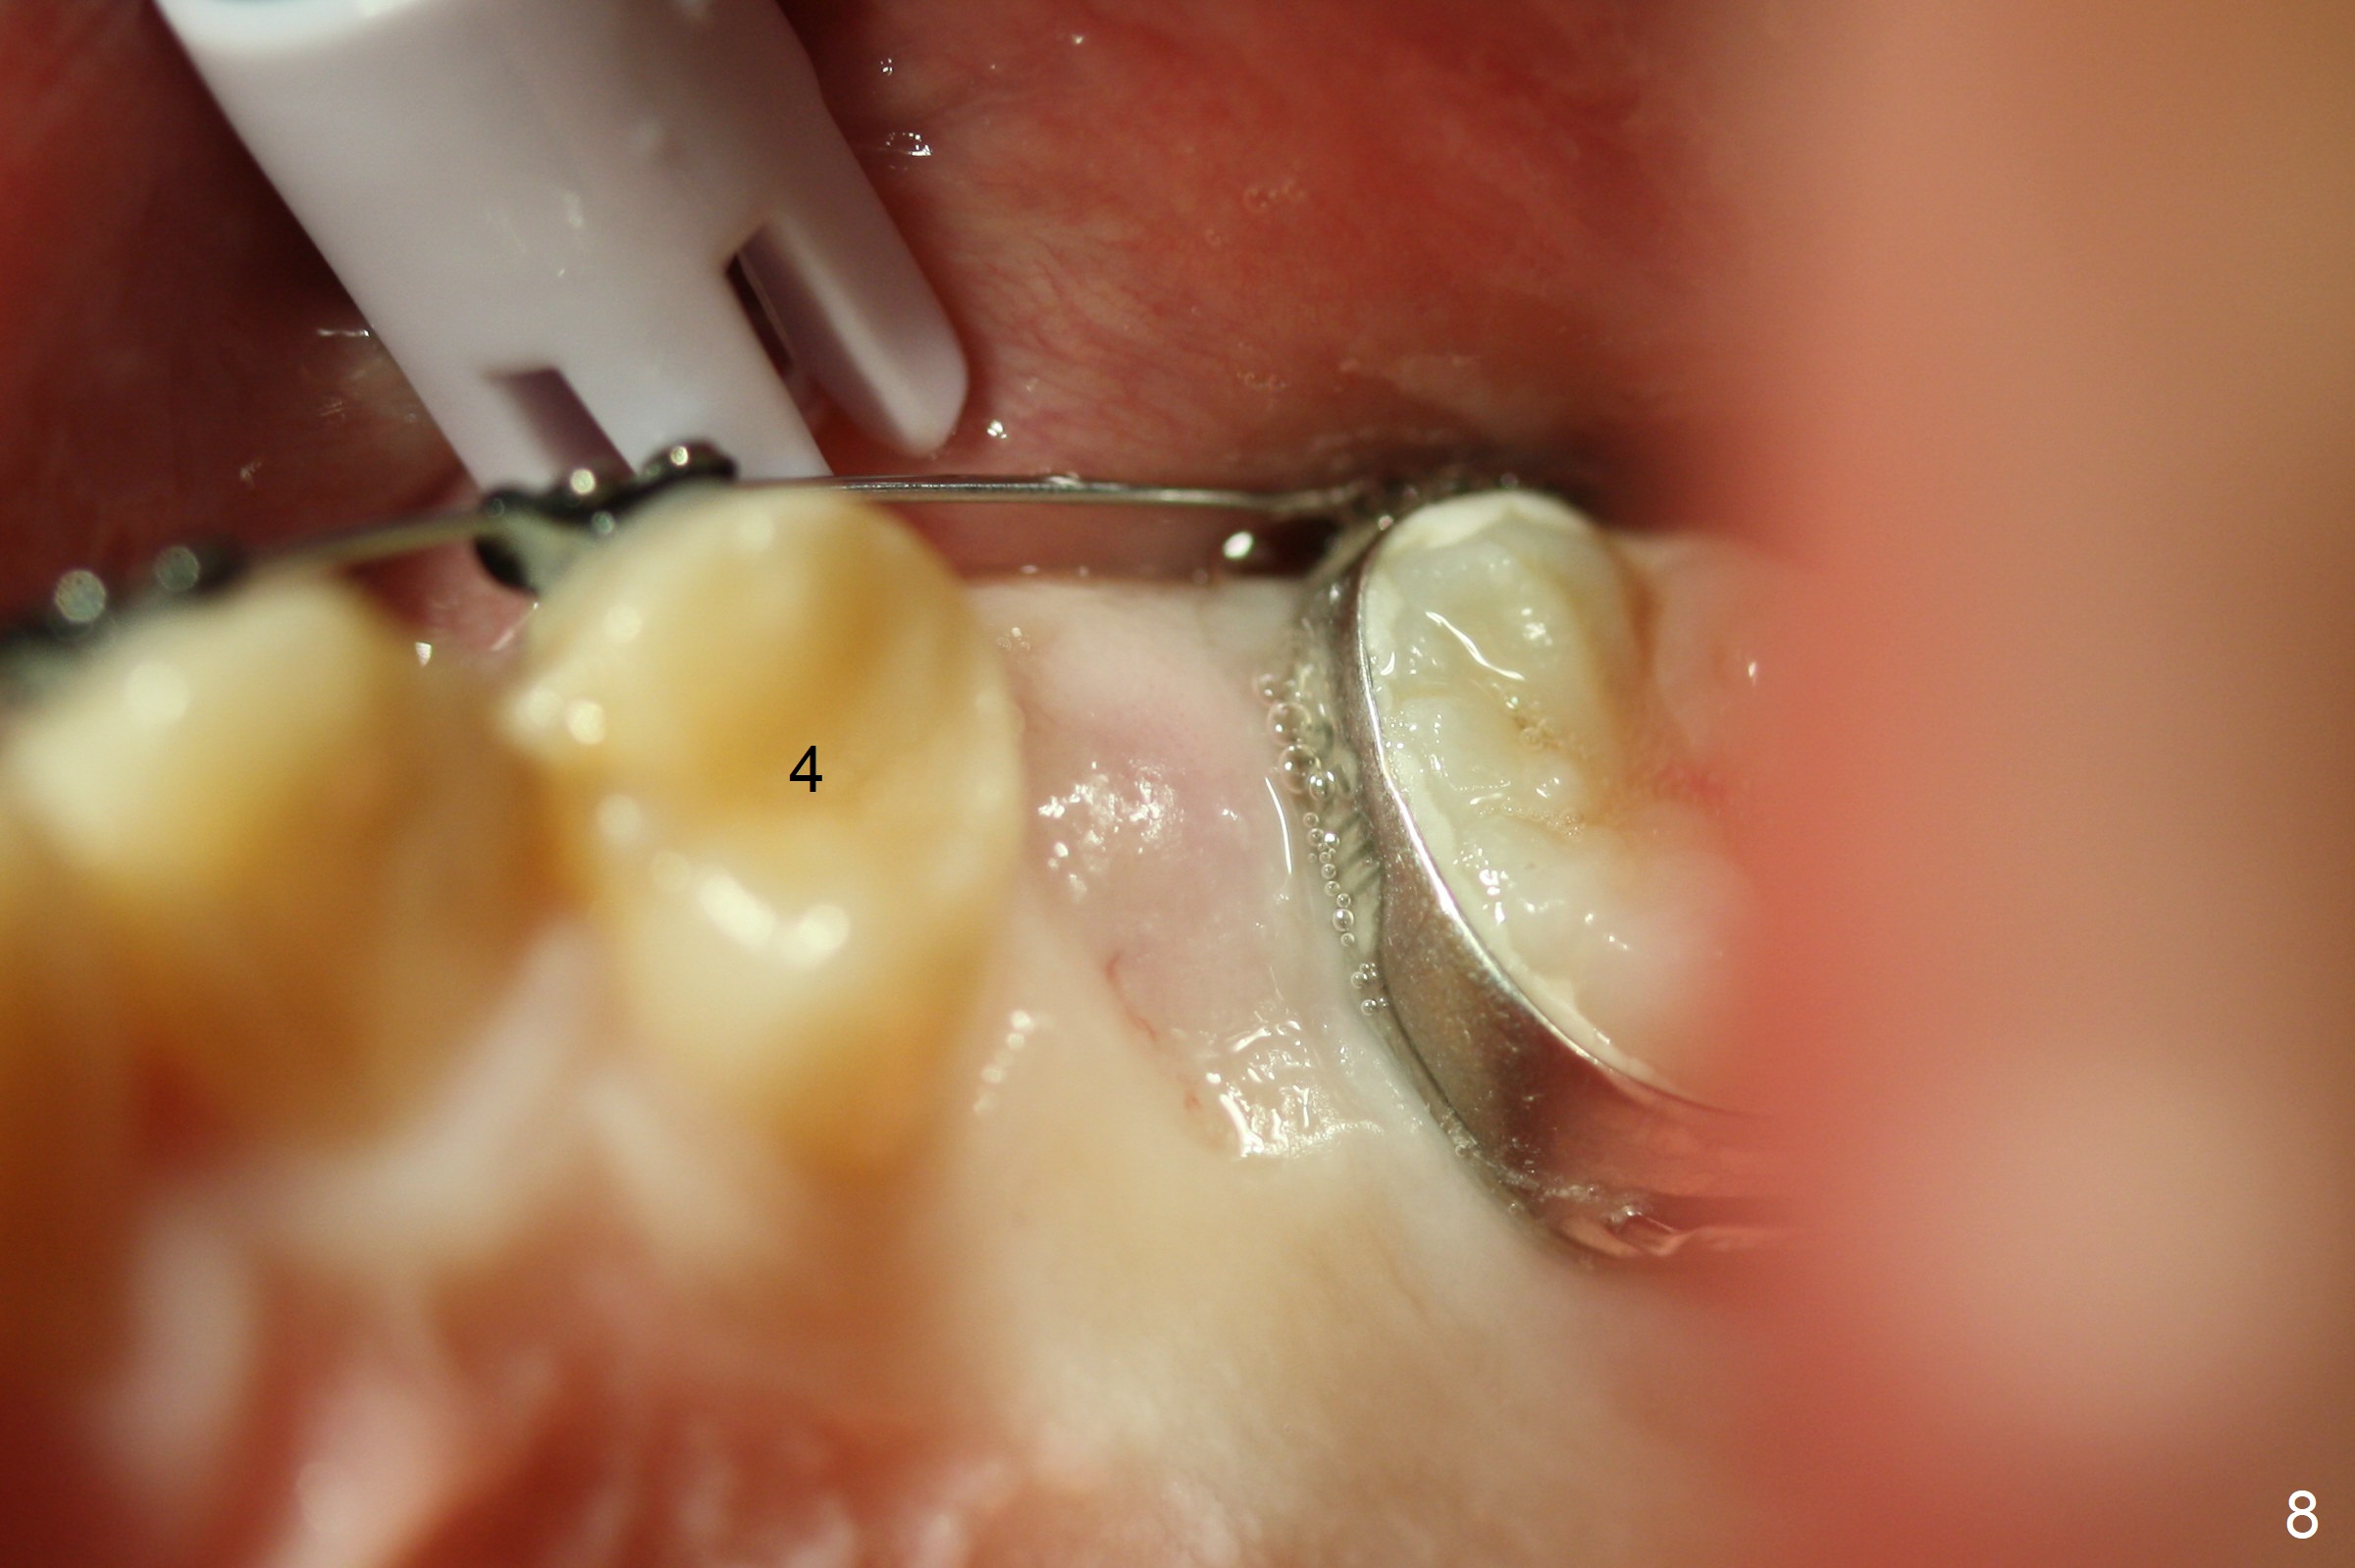

The patient and father do not favor extraction. Five months post extraction of UL E and 2 months post banding (18 ss wires), UL5 is unerupted and subgingival (Fig.8 (palatal view)) and surgically exposed with Diode laser (Fig.9). A retraction tag should have been placed to facilitate eruption. Two weeks later, the tooth is erupting; a bracket is placed. The tooth is apparently erupted 1.5 months later and is no longer engaged to the arch wire.